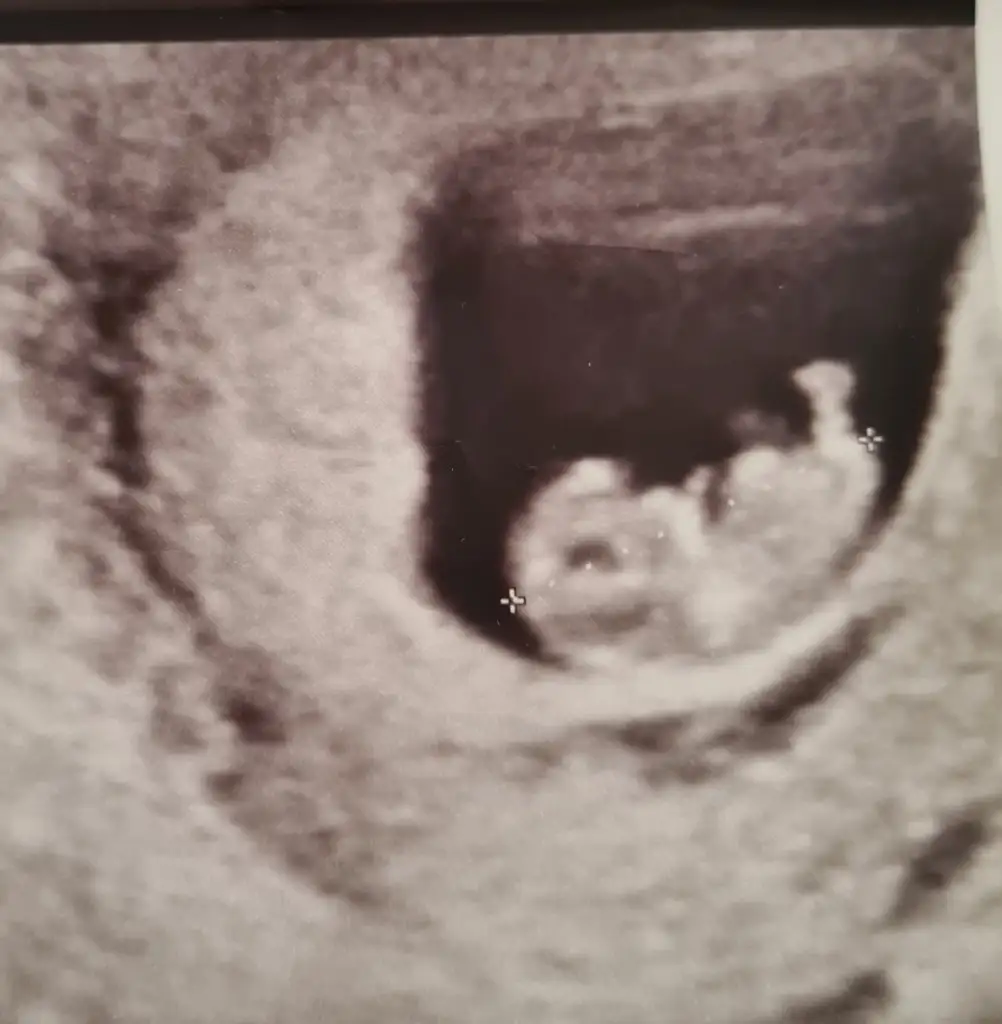

Bugün oğluma söyledikDuygusal anlar yaşadık.. Ben de heyecan yaptım. Doktora gittik, kalp atışını dinlettik yavruma Şükür olsun Gözler dolmalı, yaşlar akmalı bir sabah oldu Allah herkese nasip etsin Haftaya da ailelere soylucez inşallah. Simdi söyleyince biraz daha stres oldum. İnşallah Allah umutlarimizi boşa çıkarmasın, sağlıkla kavusalim hepimiz Bu da yavruşun fotosu ama yine cinsiyet anlaşılmıyor bence. Ne dersiniz 9+3